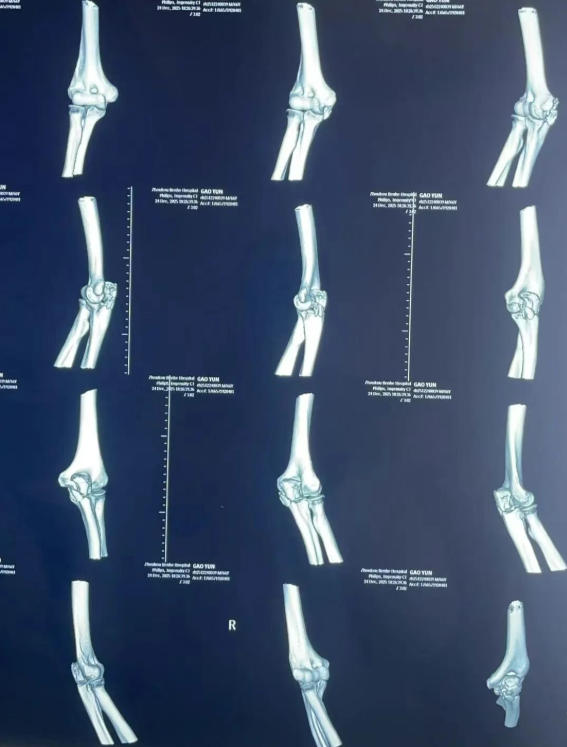

术前

一场高处坠落,让65岁的老人生命垂危:骨盆多发粉碎性骨折、髋臼中心性脱位、尺骨鹰嘴骨折,同时合并心律失常、肺挫伤、贫血与感染……伤情复杂、基础病多,救治难度极大。